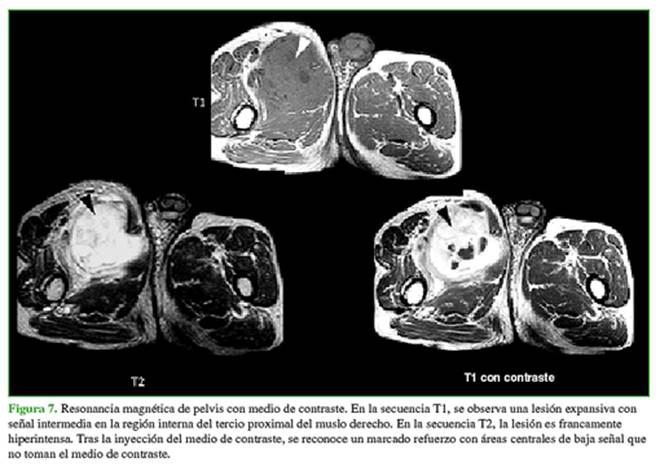

sarcomas de tejidos blandos, incluidos histiocitoma maligno o sarcoma sinovial. No hay un antecedente traumático (Figura 7).